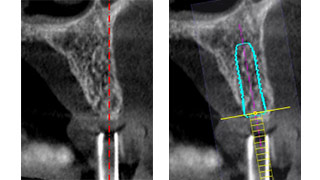

*Nouvelle approche de la chirurgie guidée : l’expertise par un logiciel de navigation 3D d’une planification sur modèle. Le projet planifié en amont sera transféré à l’image par un guide radiologique et analysé par le logiciel. Les rectifications d’axes décidées sur l’image seront facilement transposées en chirurgie par une modification du guide radiologique sur modèle. Ce guide permet un geste opératoire cadré et précis sans le stress inhérent aux actes effectués à main levée. Son coût est de 5 à 10 fois moindre que la majorité des autres systèmes.